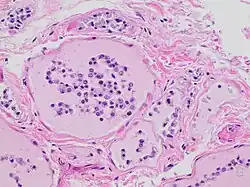

Histopathology of thyroid parenchyma with autolytic changes seen at autopsy, with thyroid follicular cells sloughing off into the follicles.